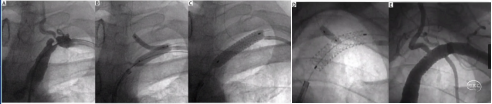

基于此,技术改良从岩谷段开始放置PRECISE支架,球囊扩张后,6F中间导管跟进至岩骨段,8mm的支架只有PRECISE可以通过6F导管,“木马”技术、叠瓦释放。

技术改良